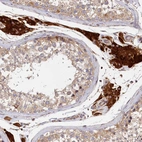

Immunohistochemical staining of human liver shows strong cytoplasmic positivity in hepatocytes.